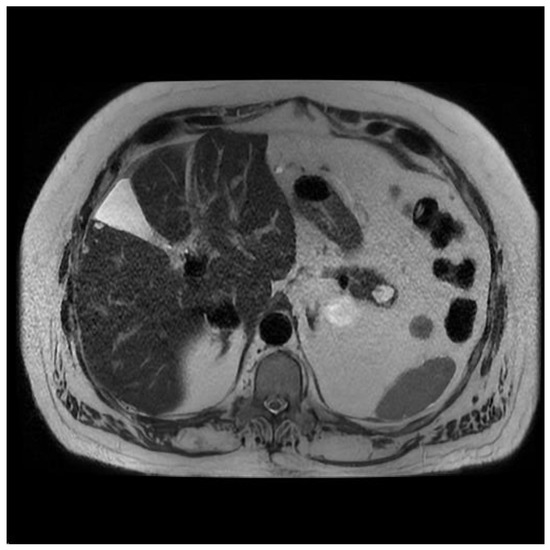

Figure 6.

MRI of cNET of the pancreas.